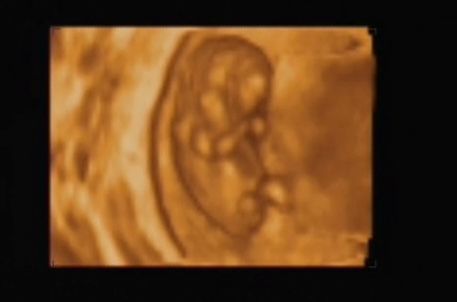

Ma voltam nyaki redő mérésen, integrált teszten. A nyaki redő 0.7 :D

A méretei alapján nem 11 hetes vagyok, hanem kb 1 héttel idősebb.

Rettenetesen ficánkolt, kaptam róla dvd-t is. Boldog vagyok, hogy megörökítettük!!! Hallottam a szive kalapálását és láthattam a kis kezeit, lábait... Velem volt a párom is, gondolhatjátok mennyire boldog volt ő is!

Rakok fel nektek képeket:

Kép Kép Kép Kép